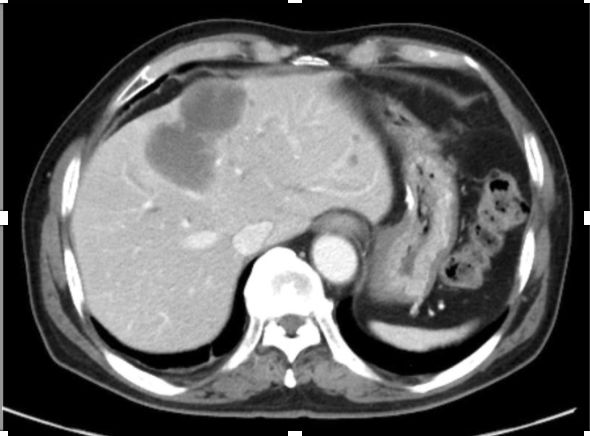

多形性平滑肌肉瘤占平滑肌肉瘤的10%, PLMS通常由老年人的骨骼肌或腹膜后组织起源,预后非常差,具有高度侵袭性。原发性肝PLMS非常罕见,占肝脏所有恶性肿瘤的0.5-2%。这例case报道的是既往诊断GIST,术后2年出现肝脏出现病灶,且在影像学考虑转移,形态非常符合GIST术后肝转移(如下图),而后并未对肝转移灶进行穿刺诊断,进行伊马替尼的治疗,在治疗无效后考虑是否存在原发耐药及其他肉瘤可能,进而进行手术治疗,术后病理组织学诊断PLMS明确。从这个病例汇报,我们可以看到,很多的肝脏的肉瘤在影像学表现相似,在治疗前,需要考虑既往病史的情况下,有必要进行穿刺再次明确病理,以区别一些相混淆的情况,另外针对耐药的转移性GIST患者而言,更要把握手术根治性切除的机会。